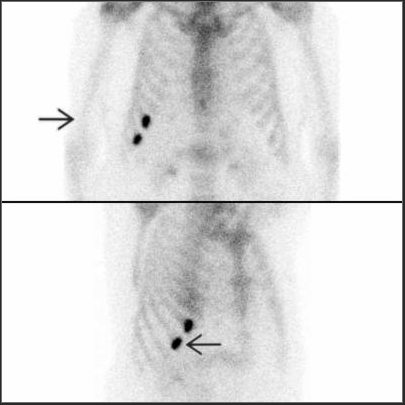

GI Bleeding Scintigraphy (Red blood cell scan)

Principles, Indication, and Examples

- Indications : To detect and localize lower GI bleeding (sensitivity 93% & specificity 95%, Laing CJ 2007)

- Radiotracer : Tc-99m labelled RBC

- Interpretation : Positive = extravasation of the radiotracer into bowel lumen

- Criteria for diagnosis of GI bleeding - Focal activity appears & conforms to bowel anatomy - Activity increases overtime - Activity movement along the bowel loop - Movement may be anterograde or retrograde